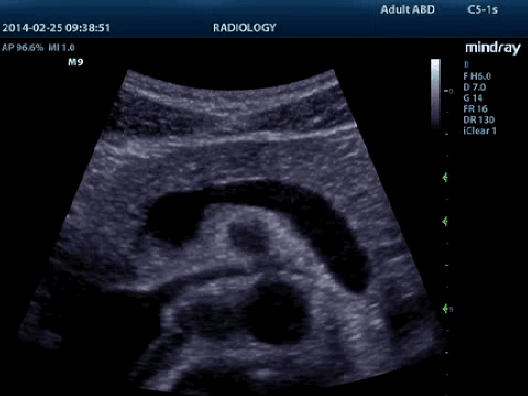

Тканевая гармоника

Используя дополнительные гармоники, генерируемые в тканях пограничных слоев, ТГ значительно увеличивает контрастное разрешение и улучшает качество изображения, особенно когда доступ к исследуемому участку затруднен.